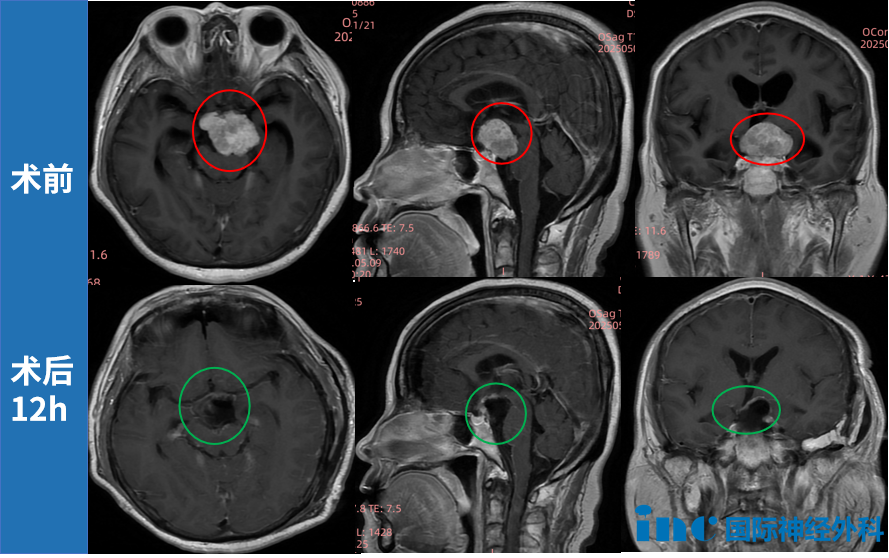

36岁的小宛,在一次体检中偶然查出脑膜瘤,一个生长于极为复杂的岩尖区、4.5cm左右的脑膜瘤,脑干和左颞叶受压……超过4cm的肿瘤已经很大了,更何况它还生长在岩尖区。岩尖在脑袋中呈金字塔形,是一块连接中后颅窝及颅底的神秘区域,邻近海绵窦、脑干等“手术禁区”。而这个区域的复杂性还体现在与很多重要的血管神经粘连紧密,不仅全切难度大,术中牵拉或误操作更极易导致神经损伤,引发术后功能障碍,如面瘫、听力丧失等,一旦引发脑出血或缺血,极有可能威胁生命。

同时,该入路在切除岩尖时降低了对颞叶、脑干或颅神经牵拉损伤的可能性,极大程度上降低术后并发症,保障了小宛的预后质量。因此,颞下岩前入路特别适用于岩斜区脑膜瘤的切除。

最终,在北京天坛医院,福教授精湛的手术操作下,肿瘤顺利切除。小宛在ICU待了短短四个多小时便能够转回普通病房。点击阅读:天坛医院手术纪实|4.5cm脑膜瘤紧压脑干成功手术,勇敢辣妈的彪悍人生!

面对如此复杂的手术挑战,INC福教授在术中借助“显微镜+神经内镜”双镜联合技术,在完好保留听力、面神经等重要功能的前提下,成功实现了肿瘤的精准切除。术后病理虽提示为2级,但因切除满意,福教授在随访中建议无需放疗,仅需定期复查即可。